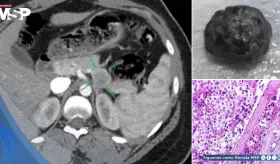

Las imágenes sugirieron un tumor con hueso, grasa y tejido cerebral dentro del recto, confirmando un diagnóstico poco común que solo se documenta en uno de cada 35.000 a 40.000 casos a nivel mundial.